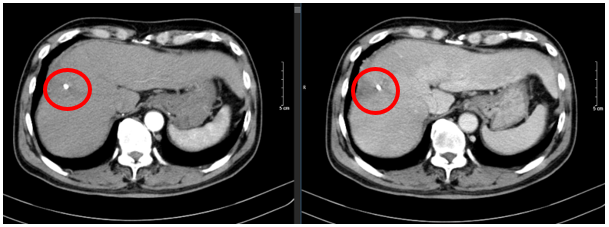

Ngày 26/12/2024: (sau 17 chu kì)

Hình 5: Hình ảnh chụp cắt lớp vi tính ổ bụng: Nhu mô vùng ngoại vi sát bao gan hạ phân thùy VII - VIII có đám (vòng tròn đỏ) giảm tỉ trọng kích thước ~ 21x48mm, trong có lắng đọng vật liệu nút mạch, sau tiêm không ngấm thuốc, không có huyết khối.

Ngày 03/03/2025: (sau 20 chu kì)

Hình 6: Hình ảnh chụp cắt lớp vi tính ổ bụng: Nhu mô vùng ngoại vi sát bao gan hạ phân thùy VII - VIII có đám (vòng tròn đỏ) giảm tỉ trọng kích thước ~ 22x45mm, trong có lắng đọng vật liệu nút mạch, sau tiêm không ngấm thuốc, không có huyết khối.

Nhận xét: Bệnh nhân đạt đáp ứng tốt với điều trị: khối u thu nhỏ kích thước đáng kể sau 20 chu kì (từ 81x51mm xuống 22x45 mm). Đánh giá theo tiêu chuẩn RECIST 1.1, bệnh đáp ứng một phần (PR – Partial Responce).